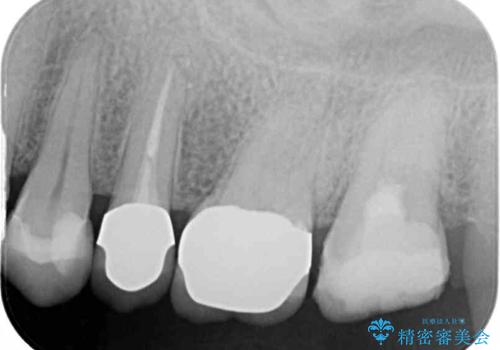

診査をしたところ、レントゲン写真よりとても大きなむし歯があることが分かりました。

虫歯が歯髄腔(神経の部屋)に達している可能性が非常に高かったため、炎症を起こしている神経組織を部分的に切除し、歯根部分の神経組織を保存する治療法が望ましいと考えられました。

処置開始前から神経組織を部分的に除去する可能性が高いことが分かっていたため、ラバーダムなどの環境を整え、無菌的環境下にて処置を進めて行きました。

虫歯は深くまで進行しており、歯冠部の神経から出血が認められました。神経を部分的に除去したところ出血が治まったので、生体親和性の非常に高いセメントにて充填し、仮封をしました。

後日状態を確認したところ、残された神経に異常がなかったため、セラミッククラウンにて補綴治療を行いました。